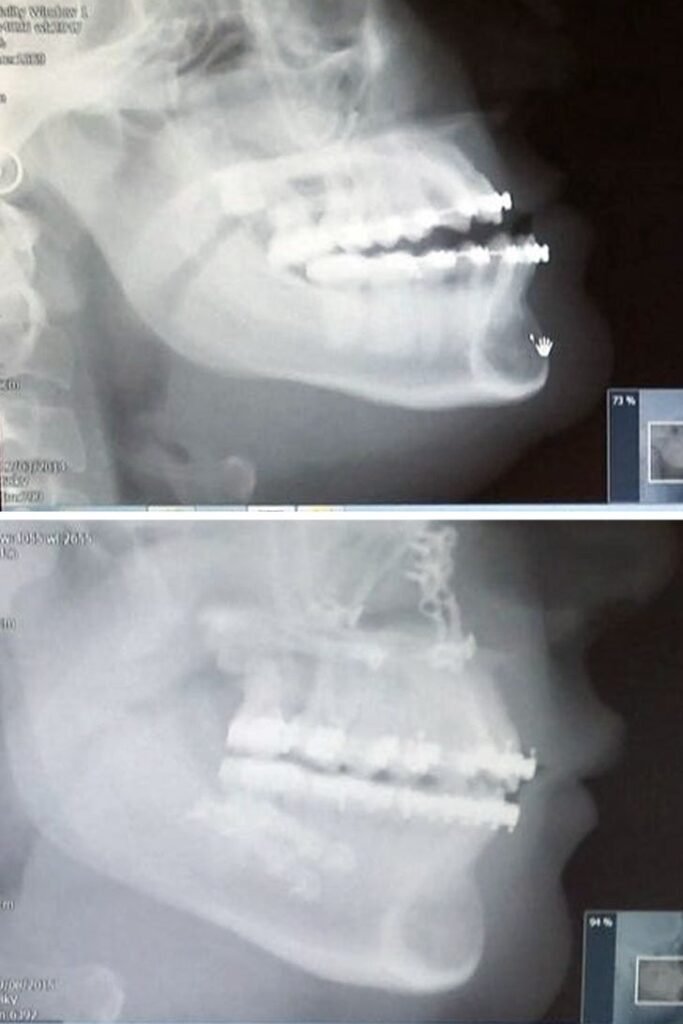

«Зробила пластику. Мій череп шимпанзе перетворився на людський»